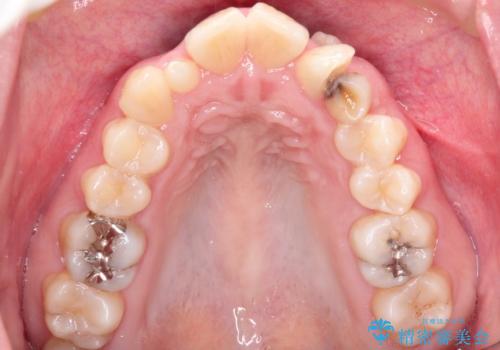

左上の犬歯が通常の位置より、かなり上方にあり、乳歯の残存と前歯のがたつきがありました。

残った乳歯と上下左右の永久歯を1本ずつ抜歯して、ワイヤーにて矯正することとしました。

犬歯も通常の位置にまで移動することができ、口元もすっきりすることができました。